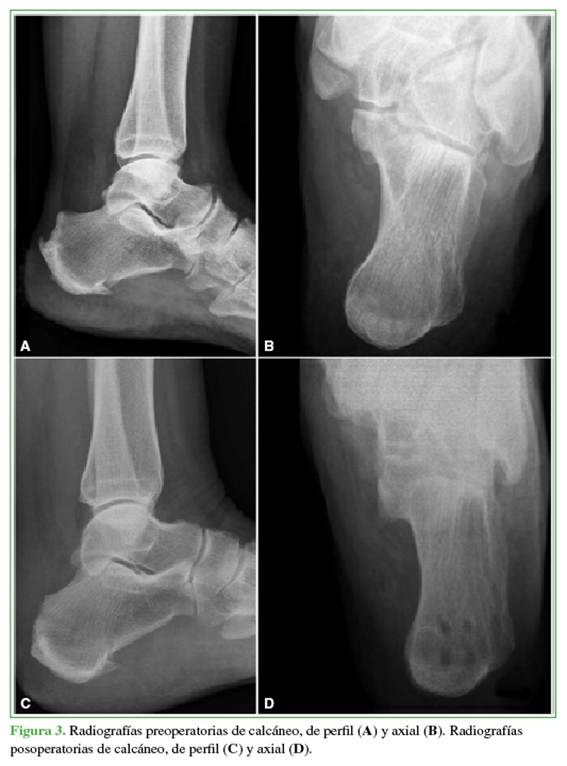

Se ubica al paciente en decúbito prono con ambas piernas sobre la mesa quirúrgica y se administra anestesia regional. Se coloca un manguito hemostático en el muslo. Se realiza un abordaje en T invertida al tendón de Aquiles, liberando la inserción enferma del tendón, si es necesario, se libera por completo. Se procede a la resección de la bursitis retrocalcánea, el desbridamiento del tendón enfermo y la resección de la deformidad de Haglund con sierra oscilante (Figura 1). Se continúa con la reinserción del remanente sano del tendón de Aquiles sobre la zona de inserción utilizando el sistema de sutura de doble hilera Achilles SpeedBridge™ Repair. Finalmente se procede al cierre por planos (Figuras 2 y 3).